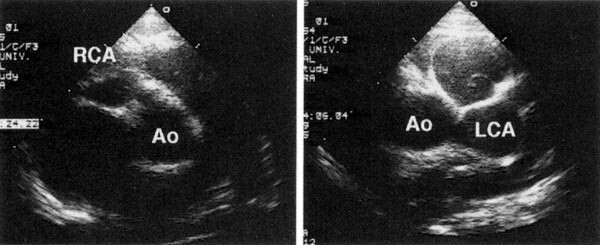

川崎病の典型的な6つの症状のうち4つの症状しか認められない場合でも、断層心エコー法や心血造影法で「冠動脈瘤」や「冠動脈の拡大」が確認され、ほかの疾患が除外されたときには「不定形例の川崎病」と診断します。